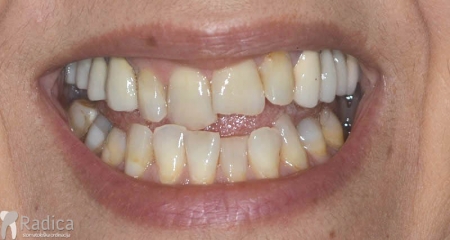

U galeriji slika su prikazani klinički slučajevi ovakvih odraslih pacijenta bilo da se radi samo o ortodontskoj terapiji ili predprotetskoj ortodonciji.